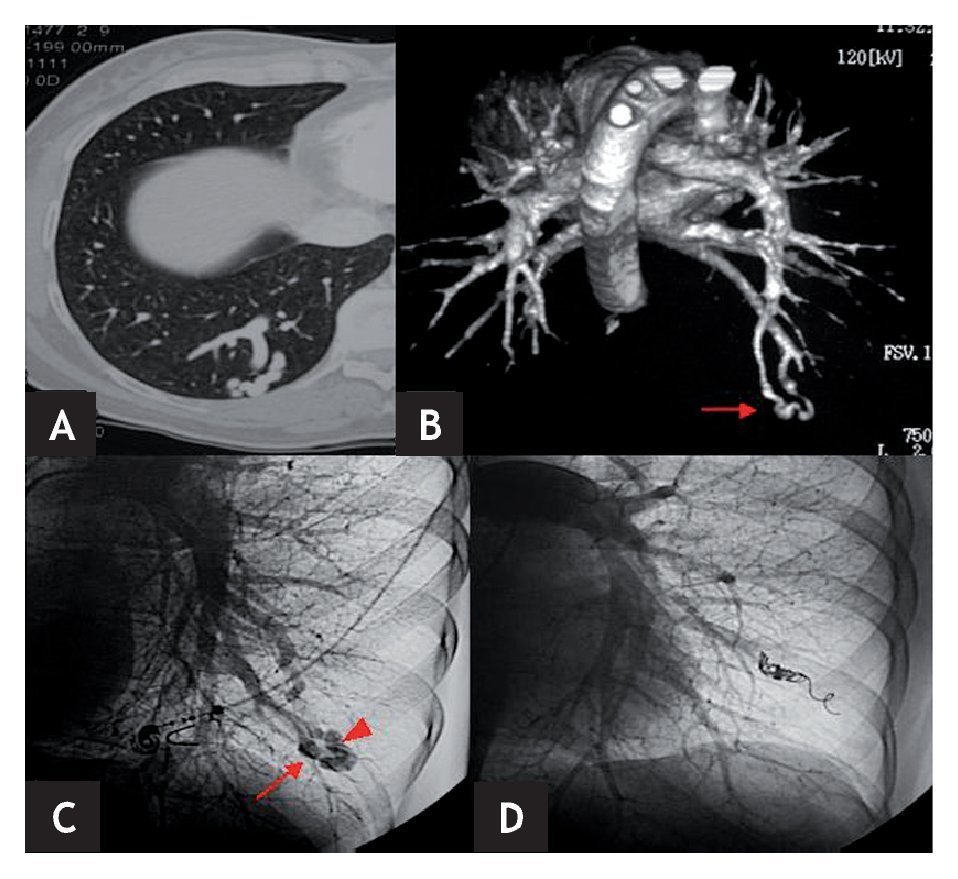

En 5 de los 6 pacientes se lograron cateterizar las ramas de aporte a la MAVP, procediéndose a su embolización y cierre (figs. 1 y 2). En el paciente restante, que presentaba malformaciones múltiples, no fue posible embolizarlas todas. Esto se debió a la imposibilidad de cateterizar algunas de las ramas de aporte porque, al encontrarse muy próximas al corazón, los latidos cardíacos movilizaban el catéter haciéndolo inestable e impidiendo la introducción segura y controlada de las espirales metálicas.

Figura 1. A y B) Paciente n.º 4. A) TC torácica con contraste: malformación arteriovenosa pulmonar (MAVP) en LID. B) Reconstrucción"volume rendering" en visión posterior en la que se observa mejor la MAVP en LID. C y D) Paciente n.º 2. C) Angiografía selectiva pulmonar izquierda donde se aprecia una MAVP simple en LII con una única rama aferente (flecha) y una única vena de drenaje (cabeza de flecha). D) Angiografía selectiva pulmonar izquierda postembolización concoils. Exclusión de la MAVP.